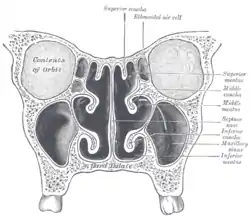

Lateral wall of nasal cavity, showing ethmoid bone in position. (Superior and middle in pink, and inferior in blue.) | |

In humans, the conchae divide the nasal airway into four groove-like air passages, and are responsible for forcing inhaled air to flow in a steady, regular pattern around the largest possible surface area of nasal mucosa. As a ciliated mucous membrane with shallow blood supply, the nasal mucosa cleans and warms the inhaled air in preparation for the lungs.

Conchae are composed of pseudostratified columnar, ciliated respiratory epithelium with a thick, vascular, and erectile glandular tissue layer.[4] The conchae are located laterally in the nasal cavities, curling medially and downward into the nasal airway. Each pair is composed of one concha in either side of the nasal cavity, divided by the septum.[4]

The superior conchae are smaller structures, connected to the middle conchae by nerve-endings, and serve to protect the olfactory bulb. The superior conchae attach to the ethmoid bone. The openings to the posterior ethmoidal sinuses exist under the superior meatus.[3] The sphenoid sinus ostium exists medial to the superior turbinate.[5]

The middle conchae are smaller but have the most complex anatomy of the nasal turbinates. They originate from the lateral edge of the cribriform plate of the ethmoid bone. They insert anteriorly into the frontal process of the maxilla and posteriorly into the perpendicular plate of the palatine bone.[6] There are three mutually perpendicular segments of the middle turbinate: from proximal to distal, there is the horizontal segment (axial plane), the basal lamella (coronal plane), and the vertical segment (sagittal plane). They project downwards over the openings of the maxillary and anterior and middle ethmoid sinuses, and act as buffers to protect the sinuses from coming in direct contact with pressurized nasal airflow. Most inhaled airflow travels between the inferior concha and the middle meatus.[3] In humans, they are usually as long as the little finger.

The inferior conchae are the largest turbinates, can be as long as the index finger in humans, and are responsible for the majority of airflow direction, humidification, heating, and filtering of air inhaled through the nose.[3]

Nasal conchae: Blocked/free Normal Nose CT Front cross section

Normal Nose CT Front cross section Coronal section of nasal cavities

In man, the three conchae define the meatuses: Inferior meatus: between inferior concha/turbinate and floor of nasal cavity; Middle meatus: between middle concha/turbinate and inferior concha; Superior meatus: between superior concha/turbinate and middle concha.